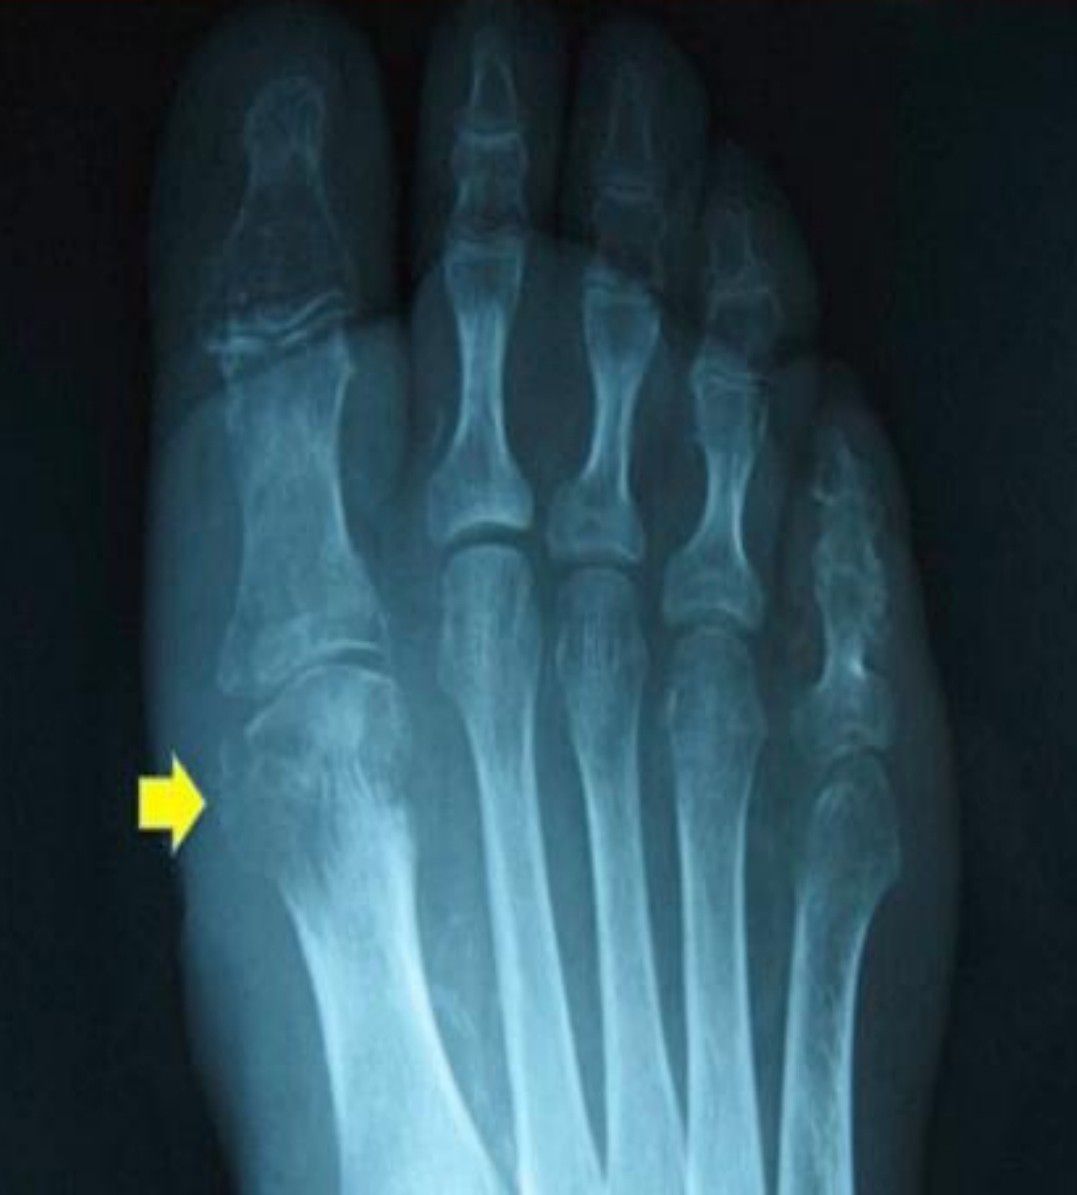

An interesting case, old person, injury with firewood in the country with 1 moth of evolution, cant walk well

Osteomyelitid?🤔🤔